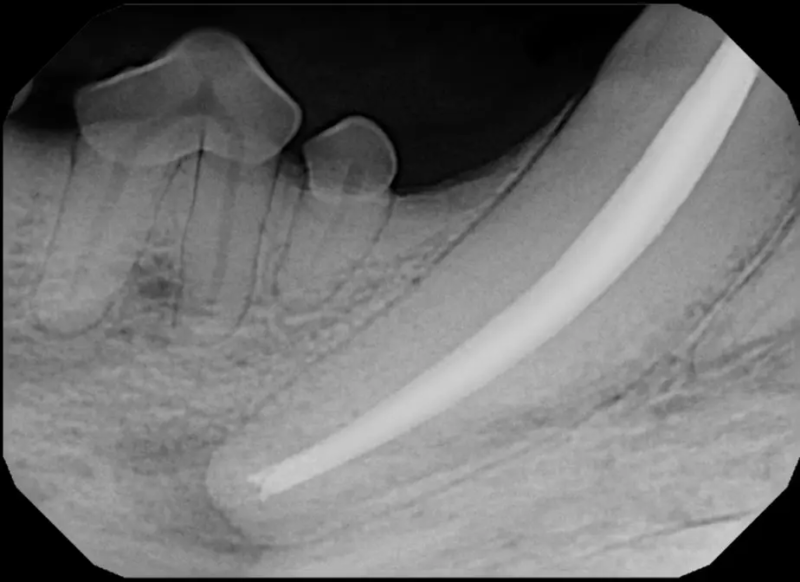

Root Canal Therapy

Root canal therapy is an excellent option for saving important teeth that have been fractured or are determined to be non-vital. The procedure is performed exactly as it would be for a human, except your pet will be dreaming peacefully under anesthesia. In many cases, root canal therapy is much easier on your pet than extraction, and preserves the structure of the tooth. It is important to have the root canal x-rayed periodically to monitor for any problems.

Sometimes teeth can be quite a challenge to remove. We routinely perform difficult extractions due to abnormally formed teeth, impacted teeth, extractions from weakened bone, and retained roots, Sometimes during a routine extraction a root can get pushed into the mandibular canal or the nasal cavity, and if that happens, we are here to get it out!